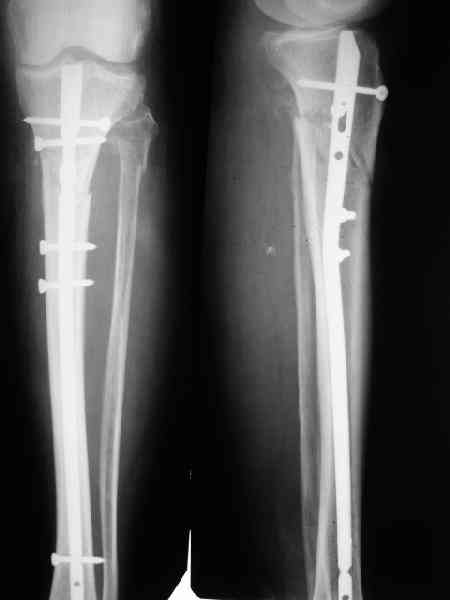

В приложении пример, дистальный отломок пружинил кзади. Два винта потому, что первый оказался чуть кпереди и не упирался в гвоздь.